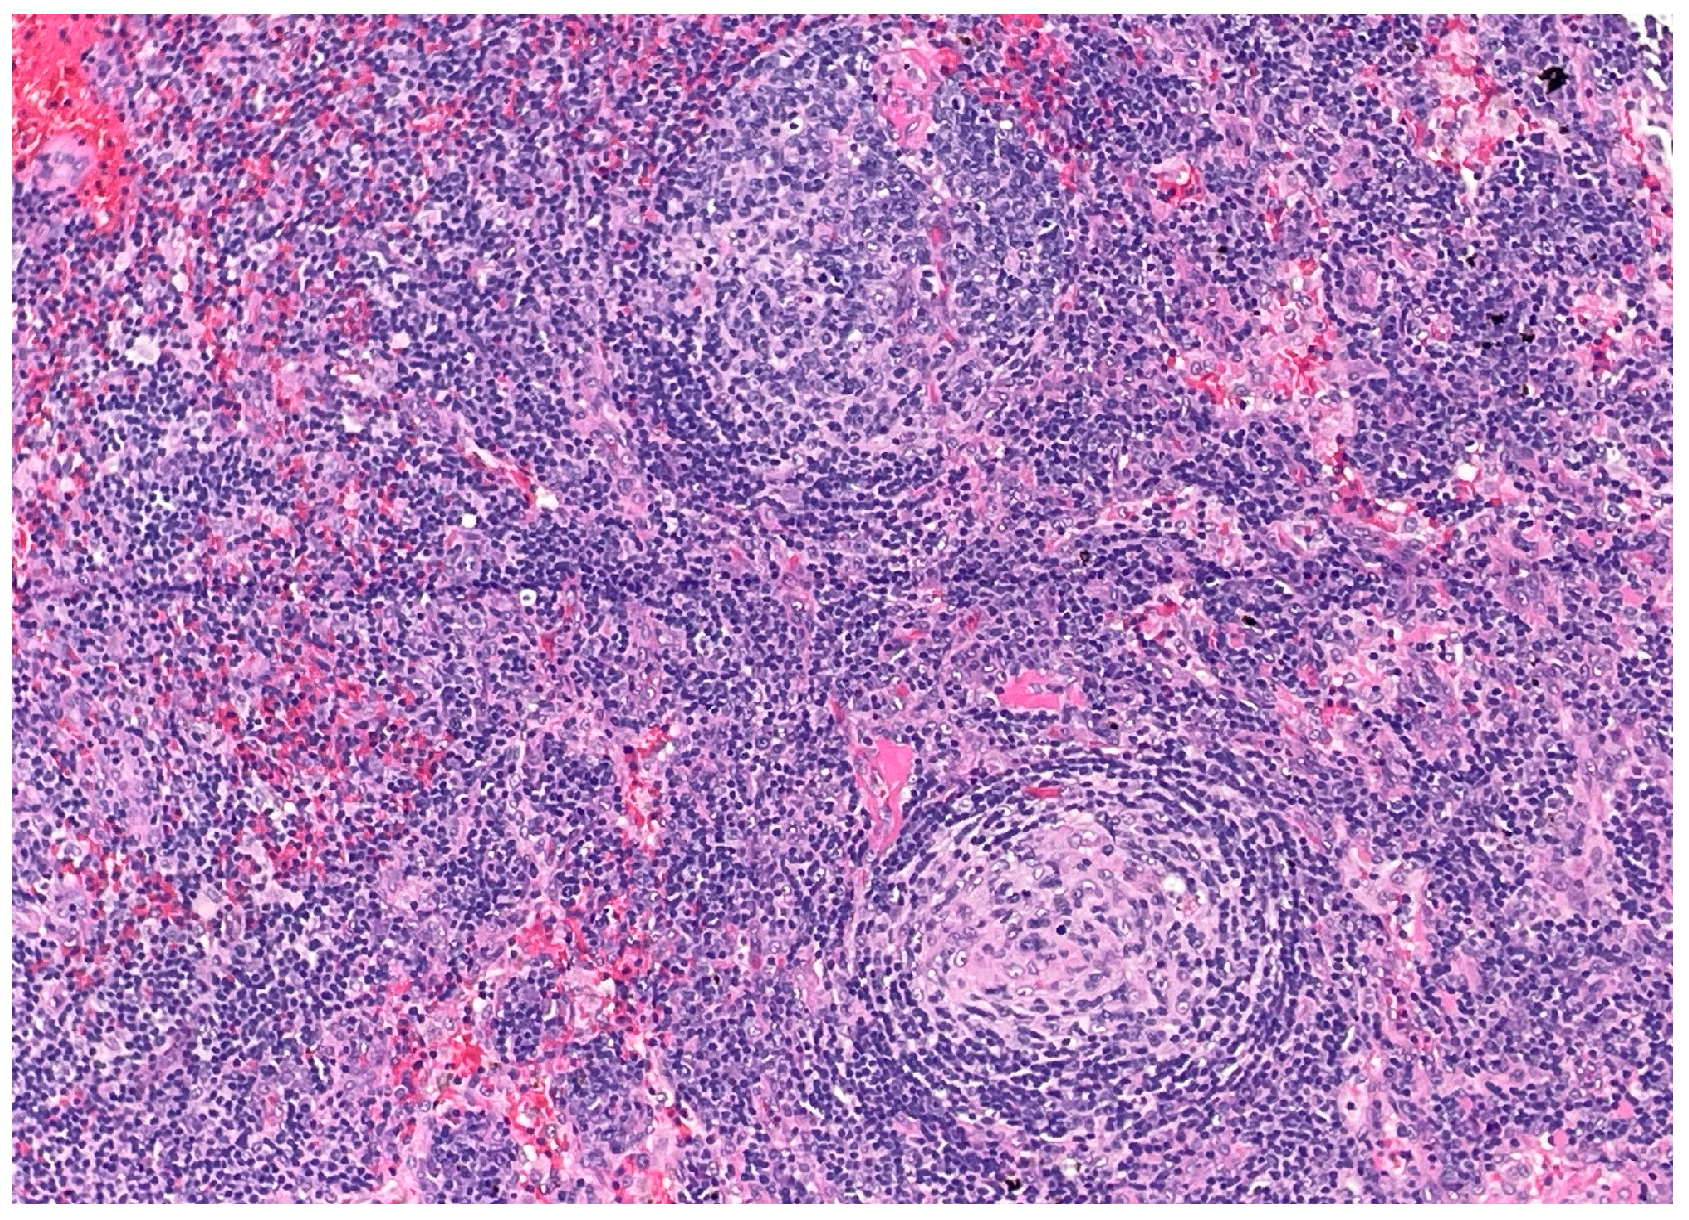

Over the following weeks, the patient developed ascites and worsening constitutional symptoms. An excisional biopsy of a lymph node was subsequently performed and demonstrated HHV-8-positive MCD, confirmed by immunohistochemical staining for LANA-1, showing scattered nuclear positivity in lymphoid cells (Figure 1). The histology also revealed characteristic “onion skinning” of mantle zone lymphocytes (Figure 2) and regressed germinal centers with increased interfollicular vascularity and hyalinization (Figure 3), findings consistent with HHV-8-associated MCD. Rituximab monotherapy was initiated, resulting in clinical improvement, resolution of the constitutional symptoms, and stabilization of ascites.

Figure 1. Immunohistochemical staining demonstrating HHV-8 (LANA-1) positivity. (40×). Scattered brown nuclear staining in lymphoid cells indicates the presence of latent HHV-8 infection, consistent with HHV-8-associated multicentric Castleman disease. This staining pattern confirms the presence of latent nuclear antigen-1 (LANA-1), a specific marker for HHV-8-infected cells.

The distinction between a core needle and excisional biopsy is critical because delays in performing excisional biopsies frequently prolong the diagnostic timeline, consequently delaying the initiation of essential treatment. In accordance with published consensus criteria, the excisional biopsy for our patient not only confirmed the diagnosis, but also revealed classic MCD histopathologic features, including the characteristic “onion skinning” mantle zones and the presence of LANA-1-positive plasmablasts [1].